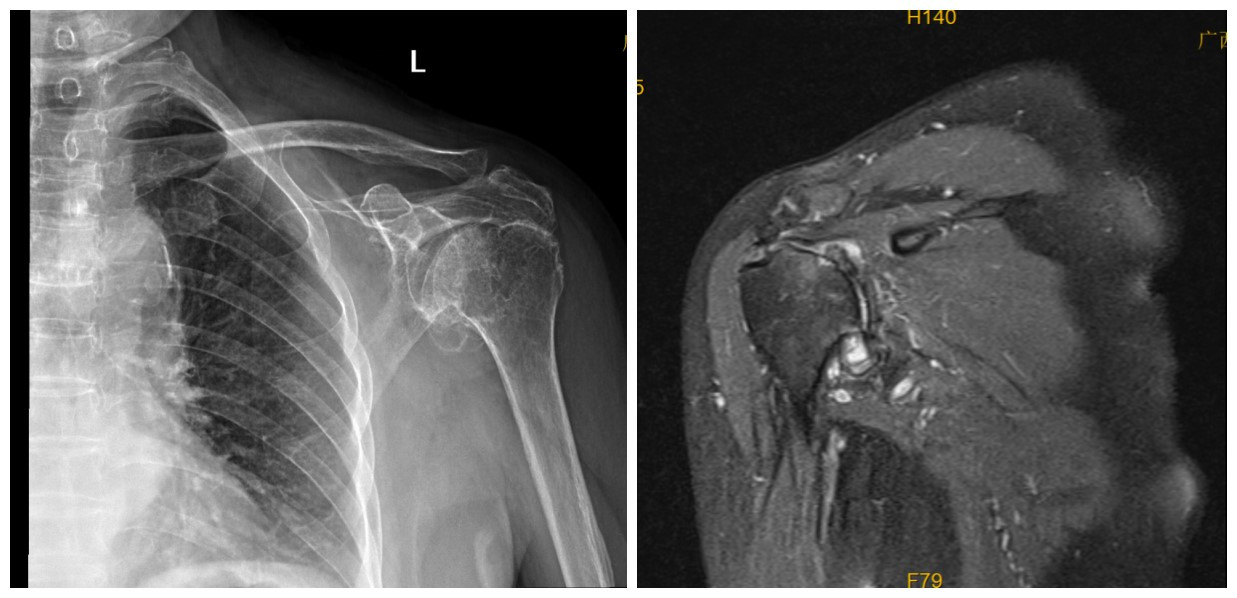

入院后关节外科/运动医学团队完善相关术前检查,考虑到婆婆年纪大,肩袖损伤严重,晚期肩关节炎,关节外科团队经过充分讨论、评估,结合病情特点,决定为其实施反肩关节置换手术,手术过程顺利,历时1.5小时,术后复查假体位置及稳定性良好,肩关节功能佳。

反肩关节置换术(Reverse Total Shoulder Arthroplasty,RTSA)是一种治疗复杂肩关节疾病的全新一代手术方式,主要适用于晚期肩关节骨性炎、巨大不可修复肩袖损伤、肩关节置换术后翻修、肱骨近端粉碎性骨折后遗症、肩关节肿瘤切除后重建等复杂病例,尤其适合高龄、基础疾病较多但需恢复基本肩关节功能的患者。手术能有效消除因肩袖损伤、肩关节炎、骨质增生等引发的顽固性疼痛,可显著改善肩关节外展、前屈等肩关节活动度,例如梳头、抬高手臂穿上衣等,有效解决患者恢复穿衣、洗漱、进食等日常生活动作,恢复生活自理能力。